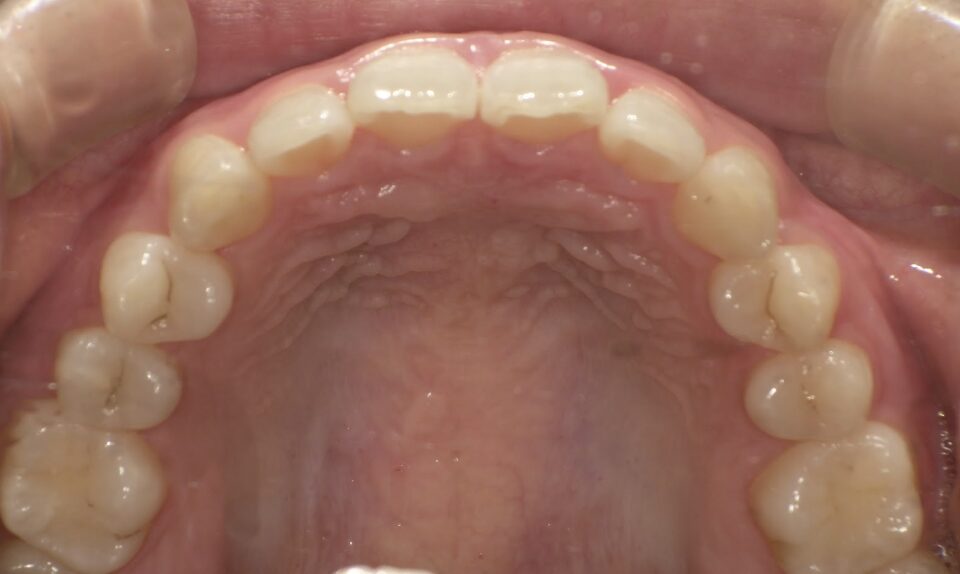

治療後

前歯のすき間が気になるを主訴に当院を受診され、前歯部空隙歯列(歯と歯の間に隙間が空いている状態)・過蓋咬合(上の歯が下の歯を深く覆いかぶさっている状態)・下顎前歯叢生(ガタガタ)を認めました。

IPRを使用してマウスピース型矯正装置(インビザライン)を使用し過蓋咬合及び叢生の改善を行いました。